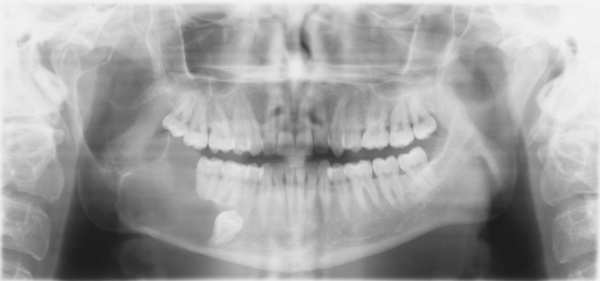

Im Jahr 2013 stellte sich nach Zuweisung durch einen niedergelassenen MKG-Chirurgen eine 44jährige Patientin in der Ambulanz für MKG-Chirurgie des Bundeswehrkrankenhauses Hamburg vor. Anamnestisch bestand seit etwa drei Jahren ein Druck- und Schmerzempfinden im Bereich des rechten Kieferwinkels sowie der rechten Unterkieferseitenzähne. Daraufhin wiederholt durch den Hauszahnarzt angefertigte Bissflügel- und Einzelzahnaufnahmen hatten keinen pathologischen Befund erbracht. Erst als die Patientin auf Grund der persistierenden Beschwerden zu einem MKG-Chirurgen überwiesen worden war, wurde in einer Panoramaschichtaufnahme eine großvolumige Zyste im Bereich des rechten Unterkieferwinkels entdeckt (Abbildung 5).

Die durch den zuweisenden Kollegen entnommene Probe erbrachte die Diagnose eines keratozystischen odontogenen Tumors. Die extraorale Untersuchung bei der stationären Aufnahme war unauffällig, der intraorale Befund ergab ein karies- und füllungsfreies Gebiss. Die ergänzend angefertigte Computertomographie des Unterkiefers zeigte eine von der Basis des Unterkiefercollums bis distal des Zahnes 44 reichende Zyste (Abbildungen 6 und 7).